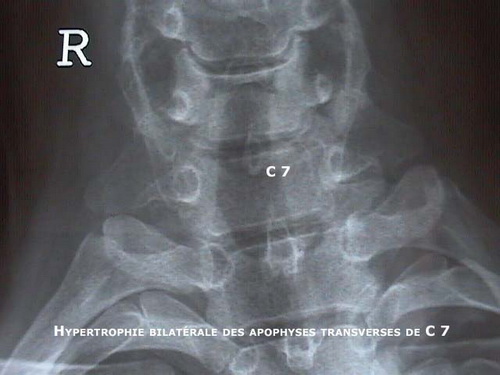

Mécanisme de production des lésions

Une lésion du genou est produite quand les petits mouvements de protection sont exagérés au point de provoquer un traumatisme.

La force peut ê...